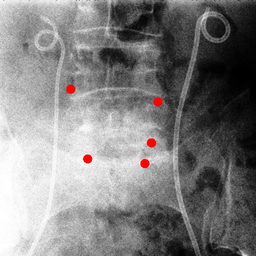

Shift-Invariant Tracking. The POINT network benefits from the shift invariant property of the convolution operation, which makes it less sensitive to the in-plane offset of the DRRs. Figure 8 shows some tracking results from the POINT network. Here the odd rows show the (a) X-ray and (b-d) DRR images. The heatmap below each DRR shows the tracking result between this DRR and the leftmost X-ray image. The red and the blue marks on the X-ray and DRR images denote the POIs. The red and the blue marks on the heatmaps are the ground truth POIs and the tracked POIs, respectively. The green blobs are the heatmap responses and they are used to generate the tracked POIs (blue) according to Equation (7). The numbers under each DRR denote the mPD scores before and after the tracking. As we can observe that the tracking results are consistently good, no matter how much initial offset there is between the DRR and the X-ray image. This shows that our POINT network indeed benefits from the POI convolution layer and provide more consistent outputs regardless of the in-plane offsets.

Refer to caption

(a)

(b) 13.6 \rightarrow 7.3

(c) 22.9 \rightarrow 9.0

(d) 37.1 \rightarrow 7.8

(e)

(f) 19.5 \rightarrow 8.7

(g) 26.0 \rightarrow 9.5

(h) 41.1 \rightarrow 11.4

(b)

(c)

(d)

Figure 8: POI tracking results. (a) X-ray image. (b-d) DRR images with different in-plane offsets. The heatmaps of the tracking results are all aligned with the X-ray images and appear similar, showing the shift-invariant property.